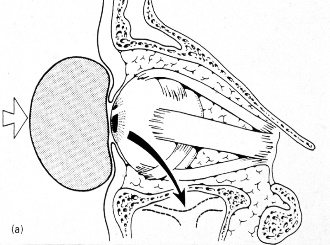

Může vzniknout trvalé omezení pohybu v určitém směru, nejčastěji vlivem narušení činnosti okohybných svalů. Nejpravděpodobnější příčinou je uskřinutí m. rectus inferior ve zlomené spodině očnice.